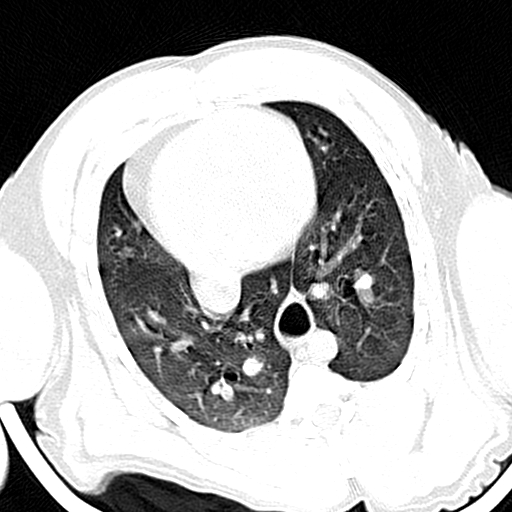

VetTom 8 provides diagnostic quality Computed Tomography (CT) images in a small mobile package. The system is capable of providing at 25 cm field-of-view with high contrast to noise giving you diagnostic confidence for soft-tissue disease and injury.

The modern Through-Silicon-Via (TSV) stacked CT detectors provide high-resolution images with low noise and high contrast, while the 40 cm gantry and 30 cm field-of-view provide additional space and information for your diagnostic needs versus VetTom 8.

The VetTom 32 has a powerful 40 kW generator, 85 cm gantry, 60 cm field-of-view, scans using proprietary batteries and can be moved to where you need imaging, especially when it may be difficult to move the patient.